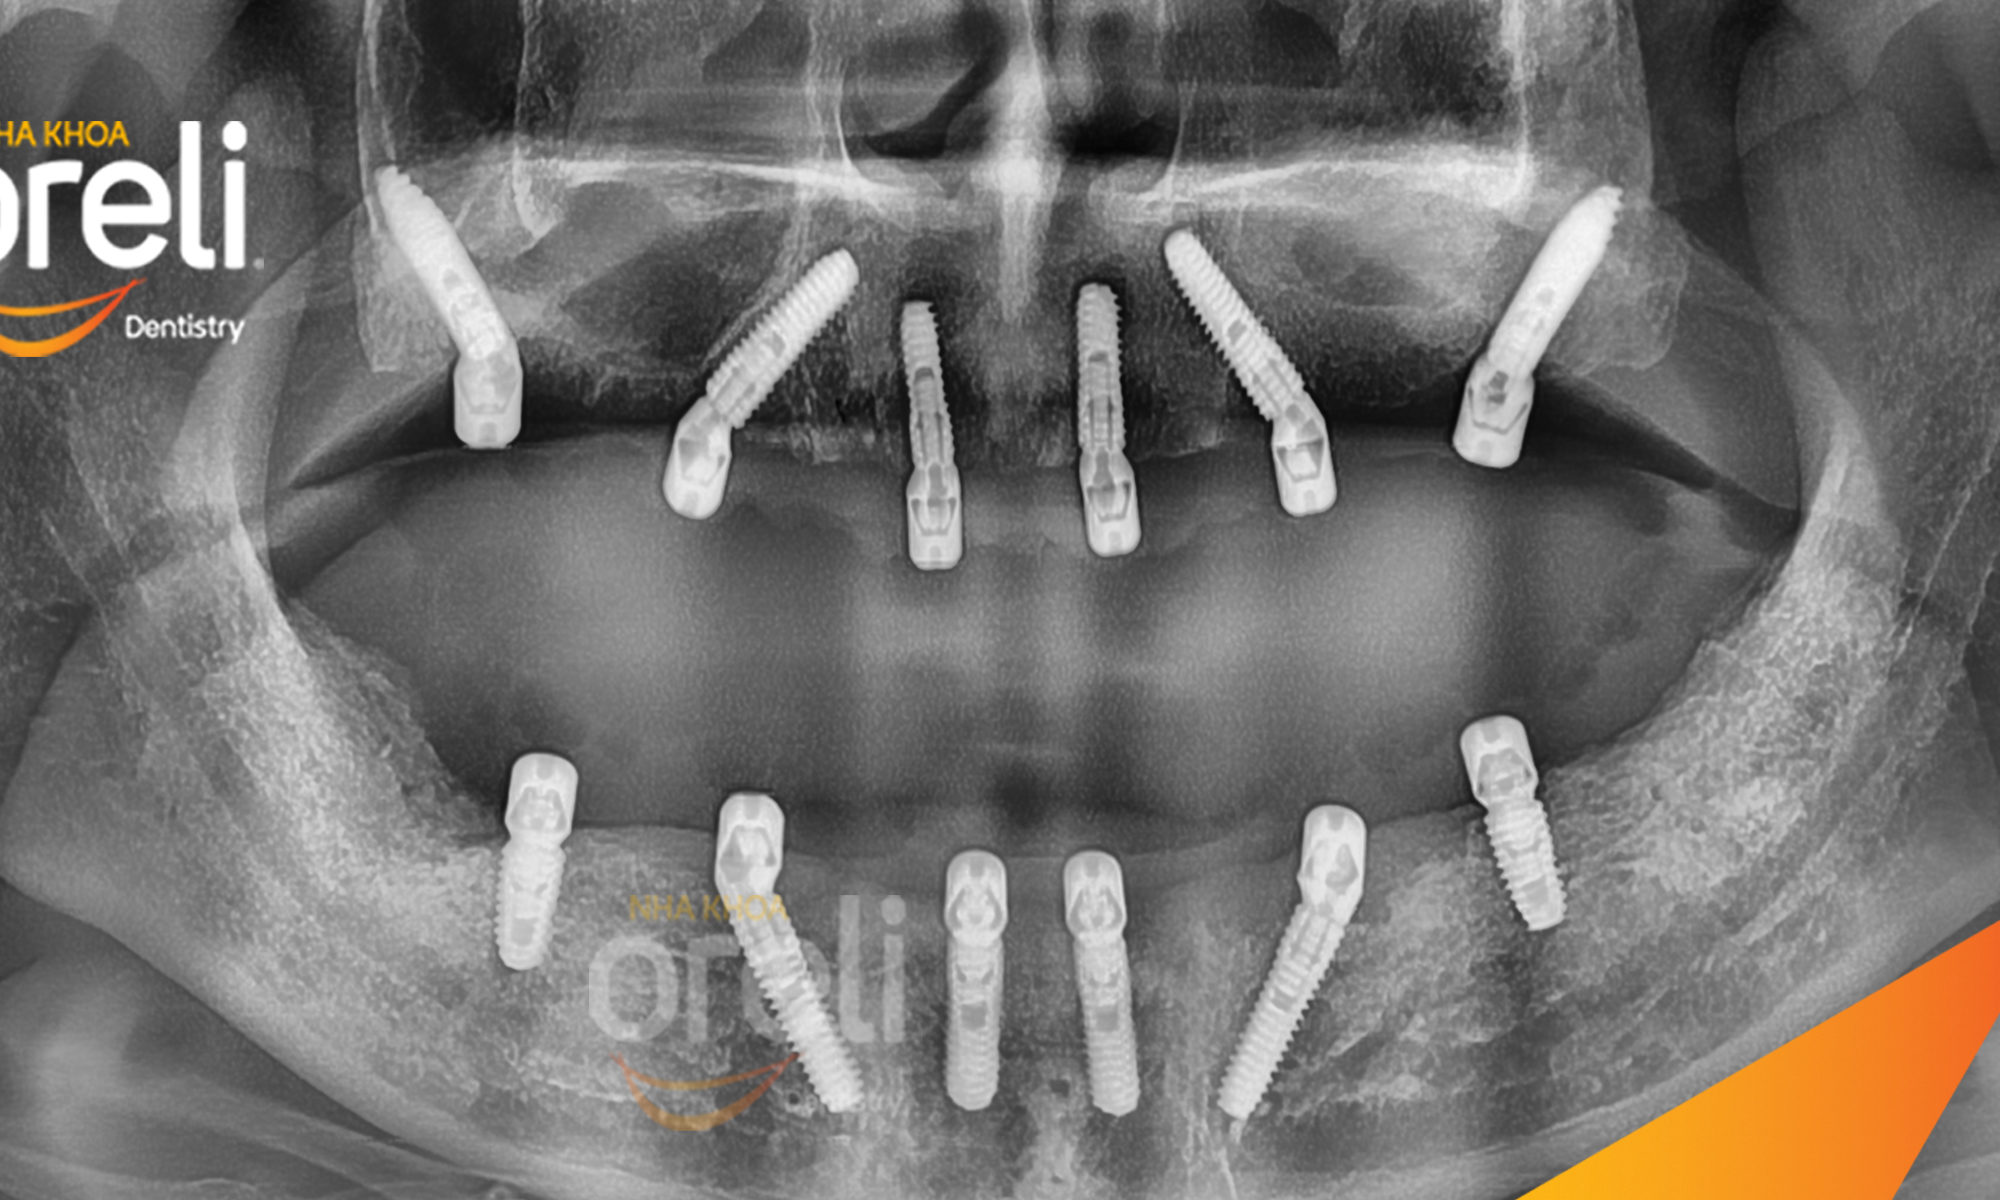

Trồng răng Implant (cấy ghép Implant) là phương pháp phục hình răng mất bằng cách đặt

trụ Implant titanium vào xương hàm, thay thế chân răng đã mất,

sau đó gắn mão sứ lên trên để tạo thành răng hoàn chỉnh.

3. Trụ Implant chính hãng

Sử dụng trụ Implant chất lượng cao, nguồn gốc rõ ràng, đảm bảo tích hợp xương tốt và an toàn lâu dài.